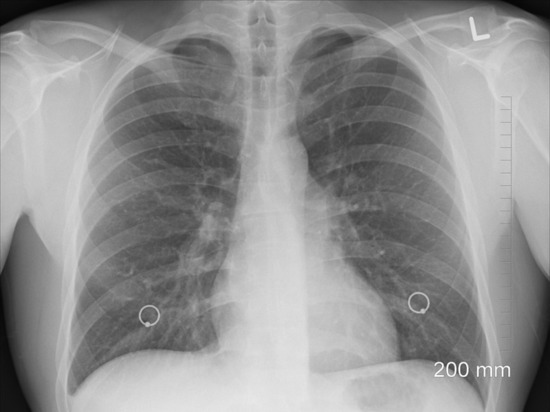

Курение